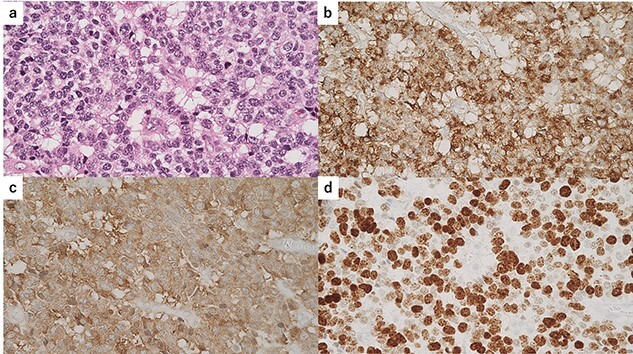

Macroscopically, there was a gray invasive nodular tumor measuring 19 × 18 × 15 mm at the distal CBD (Fig. 4). Histopathological examination showed that the tumor comprised two components; well-differentiated adenocarcinoma of the CBD mucosa (20%) and proliferation of small atypical cells forming follicular nests with invasion around the CBD wall (80%) (Fig. 5a and b). The invasion extended to the pancreas and duodenal muscular layer. Immunohistochemical examination revealed that the solid proliferative lesions of small atypical cells were positive for chromogranin A and synaptophysin (Fig. 6a–c). The Ki-67 index was ~80% (Fig. 6d). No lymph node metastasis was detected. The patient was finally diagnosed with small-cell NEC (pT2N0M0, pStage I B) of the EHBD. R0 resection was achieved pathologically and there was no recurrence for 4 months after surgery.